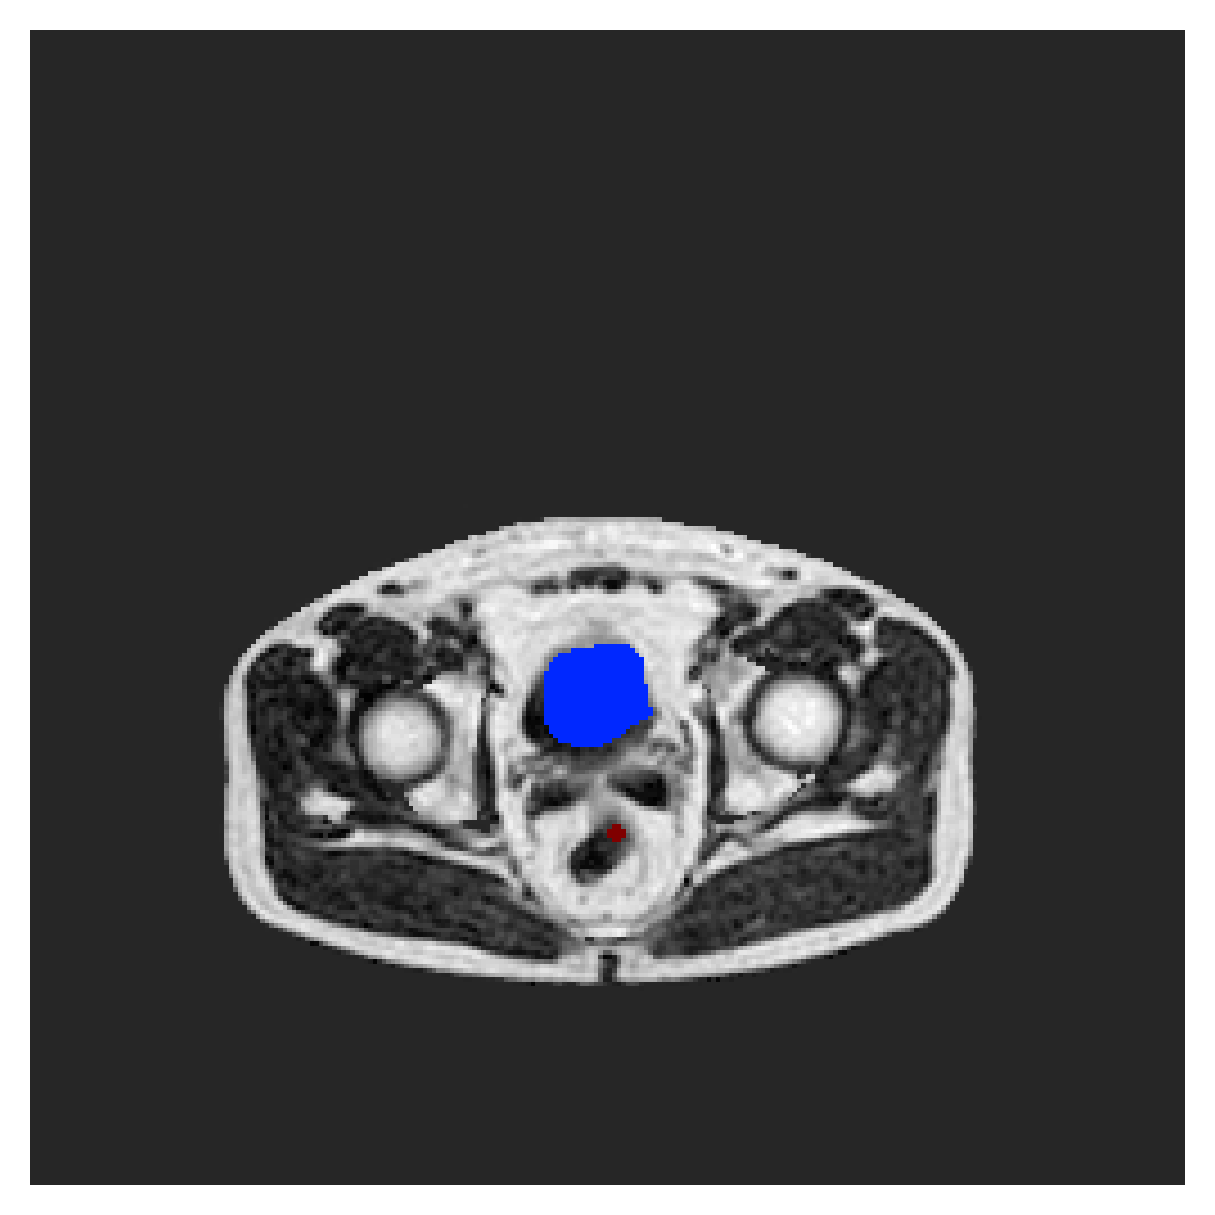

POEM

The Prospective investigation of Obesity, ENergy production and Metabolism (POEM) is a local (not currently publicly available; PI: L. Lind, see [22] for details) cohort of whole-body fat/water separated MR images. Full annotations of the liver, kidneys, bladder, pancreas and spleen are available for 50 subjects, providing a challenging segmentation dataset with heavily imbalanced classes of varying shapes. The resolution of the data is anisotropic, with reconstructed voxel size of in left-right, anterior-posterior and foot-head directions, respectively. For additional technical details regarding the acquisition and specifications of the images see [22].

The images contain two channels, one for water and one for fat content. For training, we normalize the volumes (per channel) and use 2D slices in the coronal plane, sized . The weak annotations are created synthetically, following the same procedure as described for the ACDC dataset.

5.2 Abdominal organ segmentation

Using 2D distance maps

In Table 3, the average DSC and HD95 results are shown (both using 2D and 3D distance maps) for the task of abdominal organ segmentation in POEM data (for boxplots see figures 8 and 9). We see that training with and (with distances calculated on 2D slices) performs comparably, while using and produces lower scores in both DSC and HD95 metric. On this dataset, the CRF-loss is able to compete with the boundary loss-based training strategies, even outperforming them on most classes. Most notably, all models trained with boundary loss appear to have a hard time segmenting the liver. We hypothesize this may be due to extremely severe class imbalance, as the liver covers a very large area compared to the rest of the classes. It is thus also more strongly affected by undersegmentations.